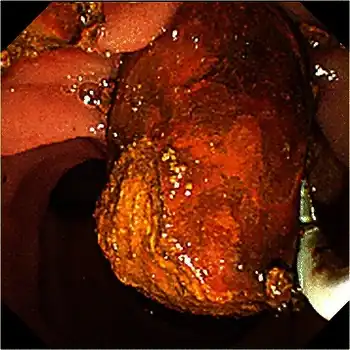

Common bile duct stone removal with a retrieval balloon

Treatment is removal of the gallstone from the bile duct using ERCP or an intraoperative cholangiogram. In these procedures, a thin tube is introduced into the common bile duct to perform a cholangiogram. If stones are identified, the surgeon inserts a tube with an inflatable balloon to widen the duct, and the stones are usually removed using either a balloon or tiny basket. A laser can be used to split big stones and make it easier to solve it using laparoscopy.[3]